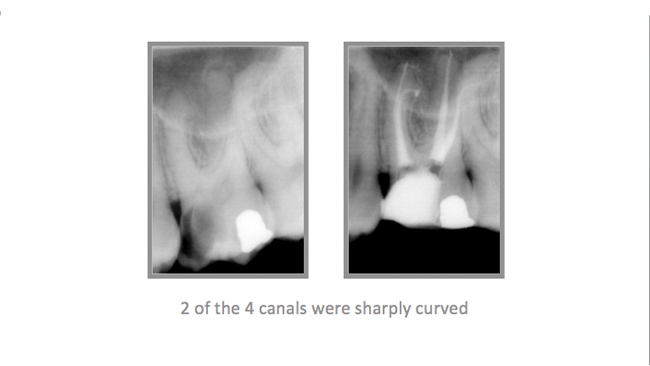

• A few Teeth Treated by Dr. Katsarsky

• A few Cases Treated by Dr. Katsarsky